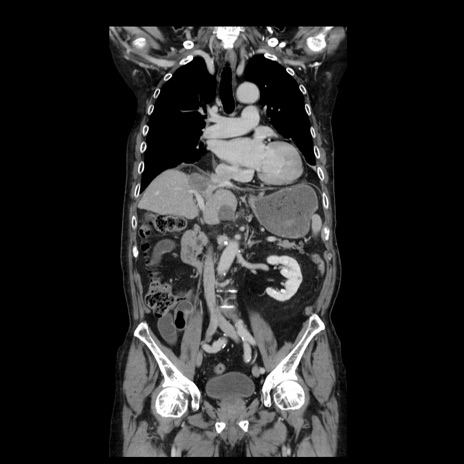

症例21(冠状断像)

【症例】70歳代男性

【主訴】腹痛

【現病歴】肝硬変・肝細胞癌にてかかりつけの方。約9時間前に食後より腹痛出現。症状が徐々に増悪し、嘔吐出現したため来院。

【既往歴】肝硬変、肝細胞癌(RFA、TACE後)

【身体所見】意識清明、表情苦悶様、BT 36℃、BP 129/78mmHg、P 88bpm、SpO2 97%(RA)、右上腹部から心窩部にかけて圧痛あり、反跳痛なし、筋性防御あり。

【データ】WBC 5800、CRP 0.16